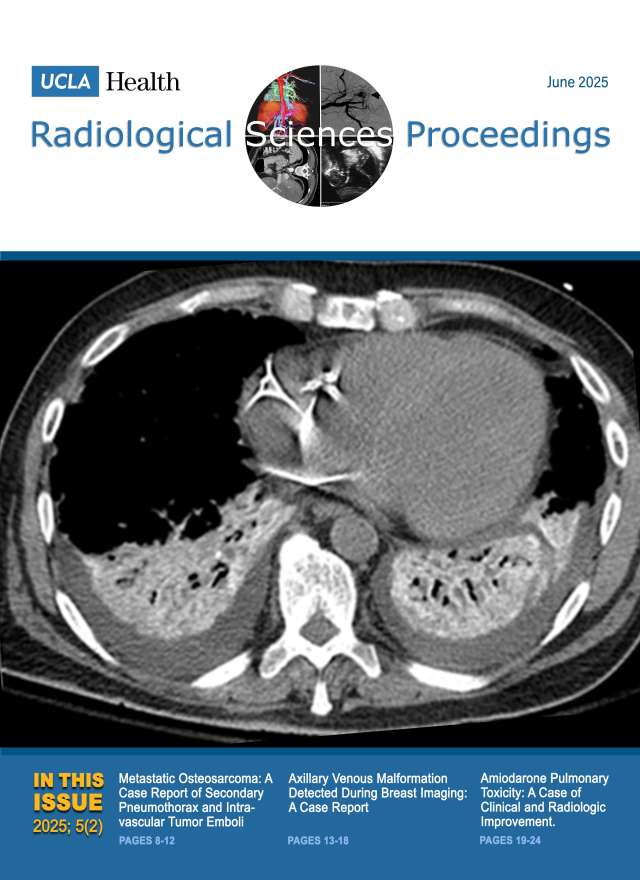

December 2024

Volume 4, Issue 4

- Smoking-Related Interstitial Lung Disease: CT Image-Based Review and Update

- Postcholecystectomy Syndrome due to Prominent Remnant of the Cystic Duct and Choledocholithiasis: A Case Report

- Kommerell Diverticulum and Agenesis of the Left Common Carotid Artery in a Patient with Dysphagia: A Case Report

- Extensive Subcutaneous Calcinosis and Hypercalcemia in the Setting of Mineral Oil-Injection-Related Foreign Body Reaction: A Case Report